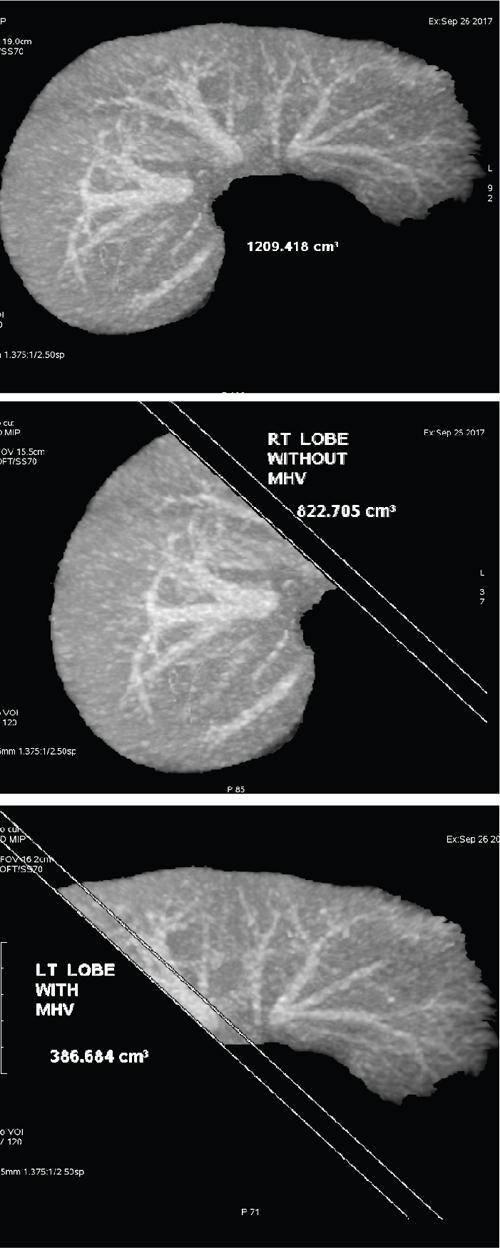

Ritu K. Kashikar, Shrinivas B. Desai Knowledge regarding normal dimensions of organs is important as visceromegaly is the first and often only abnormality in a variety of disorders. The radiologist should also be aware of normal diameters of vessels and ducts because an increase in size is usually a pointer to pathology in the organ. This chapter is a lucid review of normal sizes of organs, vessels, duct and also focuses on which section and location should size be measured to avoid interobserver variation. The liver is the largest organ in the abdomen. Hepatomegaly is a common condition and often the first clinical and imaging feature of various disorders. It is hence imperative for the radiologist to know the normal size and the section on which measurements should be taken. USG is commonly used to measure liver size. The longitudinal view is commonly used to measure liver size. The liver is considered normal in size if on longitudinal scan through the midhepatic line the liver measures 13 cm or less. This is true in approximately 93% individuals Measurement more than 15.5 cm suggests hepatomegaly in 75% cases (Figs. 9.3.1 and 9.3.2) (Table 9.3.1). Hepatomegaly is also suggested by an inferior angle of more than 45 degrees in the left lobe and more than 90 degrees in the right lobe. The normal liver measures approximately 6.5 cm first 3 months of age and reaches a size of 12.5 cm by 10–12 years of age. Liver size can be measured on unenhanced or enhanced CT. On CT the liver measures 10–12.5 cm in the midclavicular line on an average. A liver measuring more than 15.5–16 cm in the midclavicular line is considered enlarged. The midclavicular line measurement is done in coronal plane (Fig. 9.3.3). Another important measurement is the size of caudate lobe. The caudate to right lobe ratio (C/RL) is a measurement used to diagnose caudate lobe hypertrophy and right lobe atrophy which is important in the diagnosis of cirrhosis. The axial section immediately below main portal vein bifurcation is used for measurements. The following lines are drawn on the liver (Fig. 9.3.4). C/RL: In an adult patient of average weight (60 kg), the estimated liver volumes can range from 1024–1302 cm3 (Fig. 9.3.6). USG and Doppler provide important information regarding patency of artery in postoperative/transplant setting. Normal hepatic artery waveform is pulsatile and of low resistance. The normal resistive index measures 0.7. High or low resistivity index (RI) indicated pathology. The measurements of the hepatic arteries bare importance in transplant imaging. The diameter and length of the arteries are best measured on CT angiogram images. Arteries smaller in calibre than 2 mm may be difficult to anatomize. Replaced RHA is often longer in length than standard arteries. The normal diameters of the hepatic arteries are mentioned in Table 9.3.2 (Figs. 9.3.7–9.3.9). The portal venous system is valveless and hence its diameter is influenced by respiratory variations. The portal venous diameter is greatest during inspiration and hence all measurement should be made in this phase (Table 9.3.3). The diameter of portal vein has importance in diagnosing portal hypertension and USG is often used for this purpose. USG also provides other important parameters like flow velocity and volume flow which are relevant in the setting of portal hypertension. The normal portal venous velocity measures 15–18 cm/sec.(Fig. 9.3.10)

Normal hepatic volume